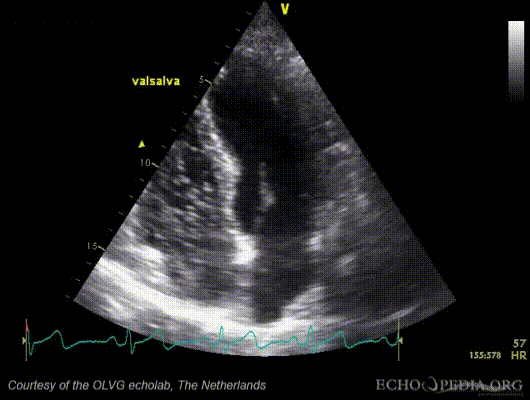

File:PFOsaline (1).gif

PFOsaline_(1).gif (530 × 400 pixels, file size: 2.29 MB, MIME type: image/gif, looped, 100 frames, 3.3 s)